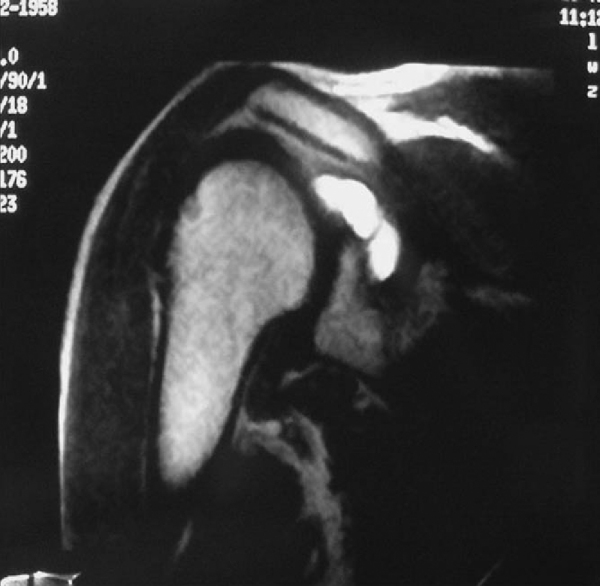

Radiographs are usually normal except in synovial osteochondromatosis, in which multiple loose bodies are noted (

Fig. 7-1

). Magnetic resonance imaging is helpful in osteochondritis dissecans lesions, cases of synovial cysts (

Fig. 7-2

), and chondrolysis. Avulsions of a Buford complex, pigmented villonodular synovitis, and articular cartilage fractures will not show up on most radiographic tests. Glenohumeral avulsions are visualized by arthrography, and the coracoid fracture is best noted on computed tomographic scans.